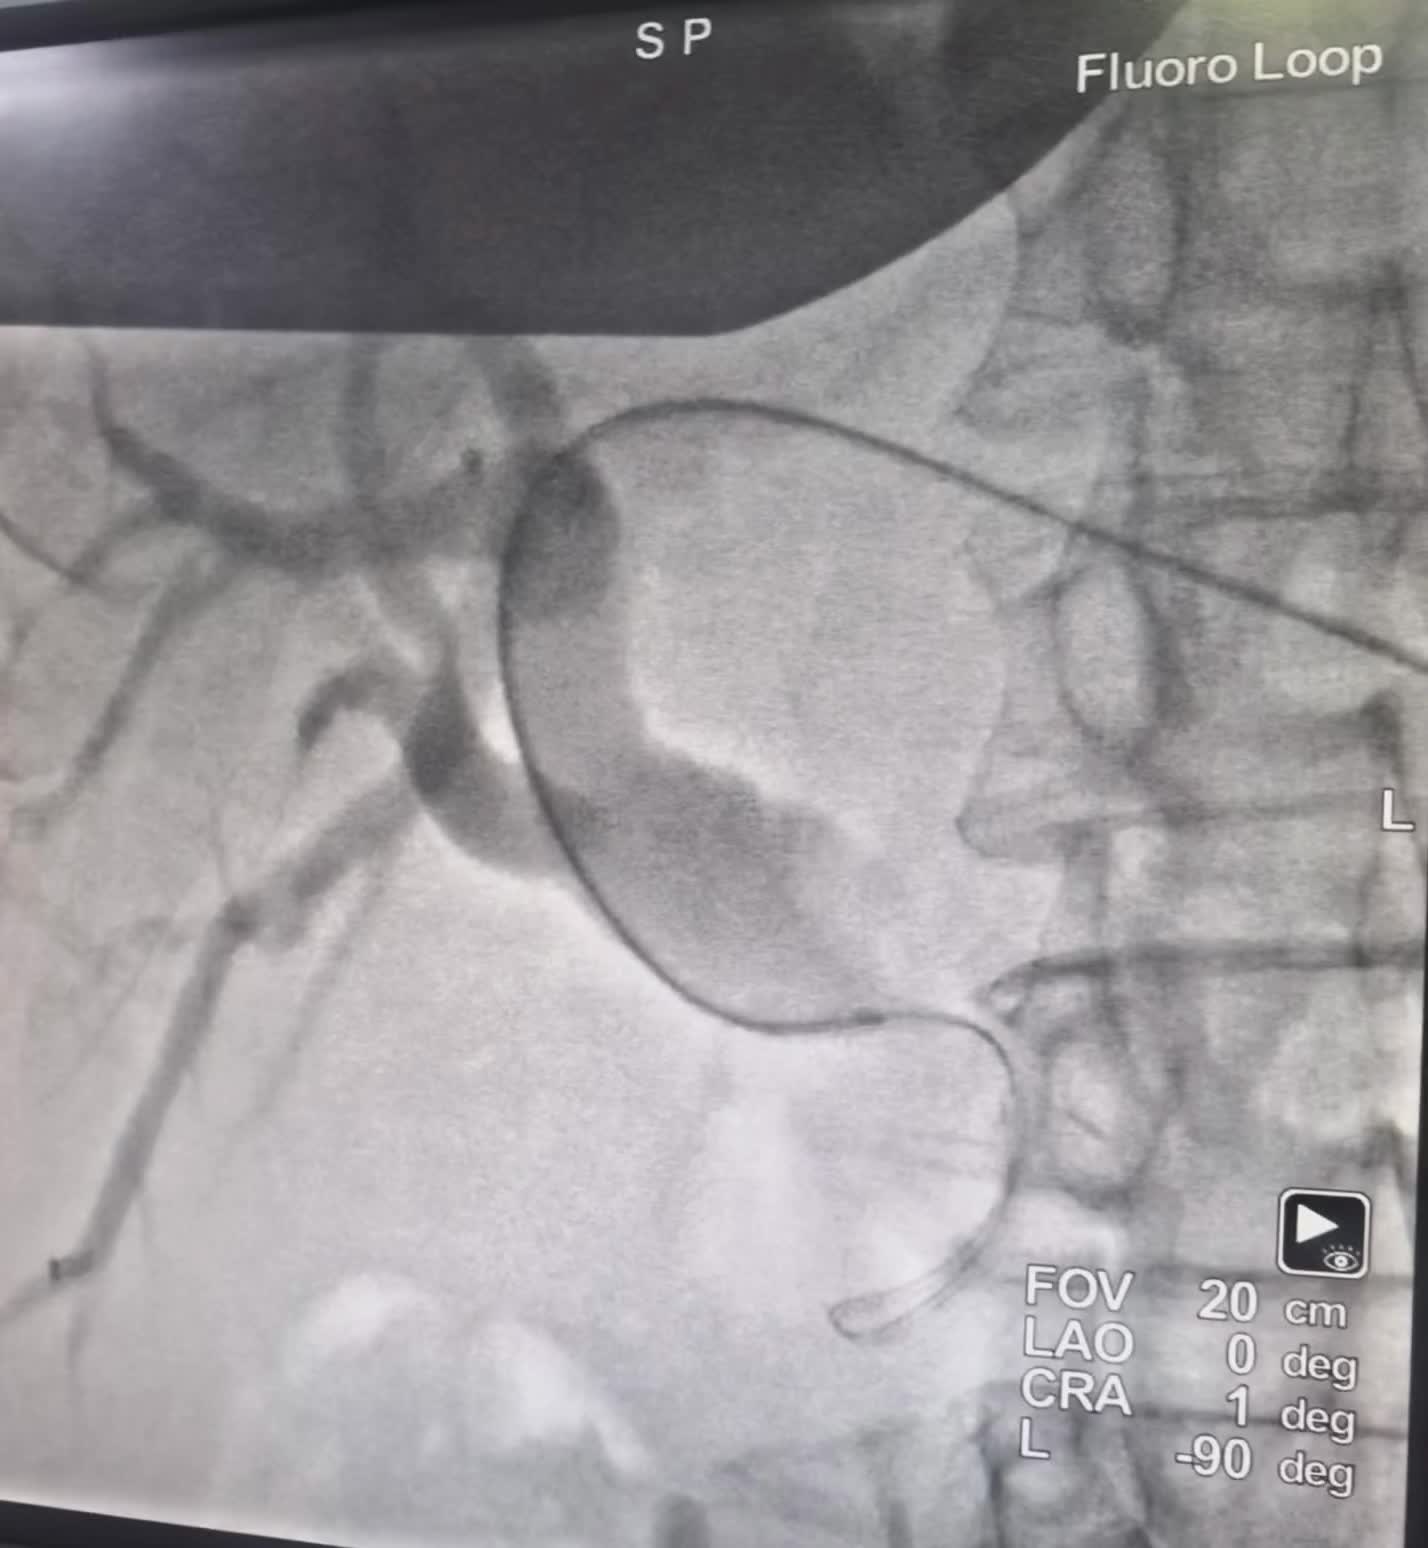

一例胰头癌压迫胆管引起的梗阻性黄胆伴胆管 一例胰头癌压迫胆管引起的梗阻性黄胆伴胆管感染,经过不断艰辛的努力打通梗阻的胆管,置入胆道内外引流导管。快速退黄控制感染最有效的方法。